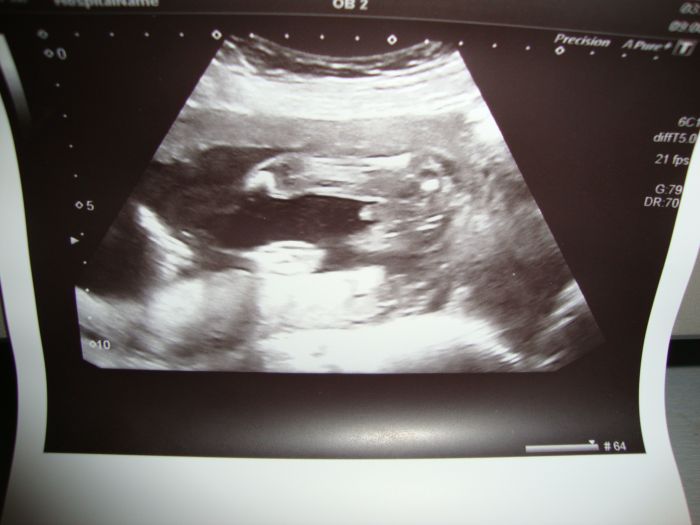

Ahojky holky hlásím příchod z velkého ultrazvuku,kde mi pan doktor vyvrátil tvrzení paní doktorky,že to bude holčička a vyfotil mi pindíka.....................takže čekáme chlapečka,je v pořádku a už má skoro 500g. Kluci to naštěstí vzali v pohodě a už vymýšlí jméno. Sono tobě držím palečky,aby jsi byla s miminkem v pořádku!!!!! Dávejte na sebe holky pozor!!!!

Ahoj Květo, tak ta fotečka je jednoznačná - snad to není zamotaná pupeční šňůra - ale nevypadá to

Květuš tak ten UZ je opravdu jednoznačný

[176124] Ahojky Leni to nevím kolik měří,pochybuju,že by ho změřili,protože byl pěkně v klubíčku,ale jinak se podle ultrazvuku předcházím o pár dní.

Jinak holky první zjištění dalšího chlapa,co vám mám říkat,byla jsem přešlá,ale hlavně,že vím že je v pořádku a jméno to bude problém doted to byla Verunka,tak jsem zvědavá s čím kluci přijdou.Ale je to krásný pohled na toho mrňavého mimozemšťana při ultrazvuku.Já dneska nejsem vůbec schopná reagovat,tohle počasí mi nedělá dobře.

[176130] Jinak Jani,to uprostřed je opravdu pindík

,je to pohled jako ze záchodové mísy když si chlap sedne